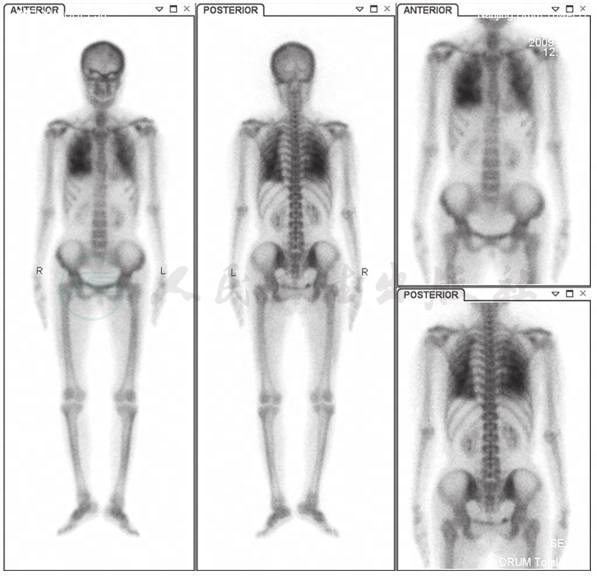

99mTc-MDP骨闪烁显像:双肺野可见类似骨显像影(图7)。

图7 99mTc-MDP骨闪烁显像

引自:主编:.呼吸系统疑难病例诊疗辨析.第1版.ISBN:978-7-117-26415-0

术后11个月,胸部CT示双肺多发斑片影明显减少,左下肺钙化及心室壁钙化较前减轻(图9);99mTc-MDP骨闪烁显像示双肺野骨外显影较前好转(图10)。

图10 术后11个月99mTc-MDP骨闪烁显像

MPC的诊断较困难,特别对于钙-磷乘积正常者,若排除了其他可能引起肺钙化的疾病,如结核、肺泡微结石症、矽肺,需要考虑MPC的可能。99mTc-MDP骨闪烁显像术有助于协助诊断。钙-磷乘积是指血钙、血磷值[以百分毫克(mg/dl)为单位)的乘积,正常值为30~40。其中,[Ca]1mmol/L= 4mg/dl;[P]1mmol/L=3.1mg/dl。若([Ca]×[P])>40,则钙和磷以骨盐形式沉积于骨组织;若([Ca]×[P])<35,则妨碍骨的钙化,甚至可使骨盐溶解,影响成骨。

根据辅助检查结果,考虑本病例病因为原发性甲状旁腺功能亢进,手术切除甲状旁腺,病理检查显示为甲状旁腺腺瘤。甲状旁腺激素分泌过多可致高钙、低磷。本例患者钙磷乘积在正常范围内,经支气管肺活检见肺泡腔及肺泡隔有多量钙化物沉积,胸部CT见两肺散在斑片状影,99mTc-MDP骨闪烁显像见双侧肺野骨外显影,排除了肺结核、矽肺等常见疾病。因此,本病例诊断为甲状旁腺腺瘤伴发转移性肺钙化。

MPC的治疗以控制钙磷平衡为主,积极治疗引起钙磷代谢紊乱的病因,如慢性肾功能不全、原发或继发性甲状旁腺功能亢进等,病情可好转。本病例影响钙磷平衡的主要原因为甲状旁腺腺瘤,手术切除病变的甲状旁腺,术后11个月复查胸部CT显示病灶较前明显吸收。